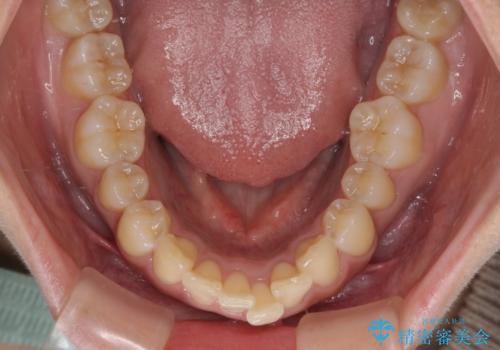

- 前方に主張した前歯2本を気にして来院された患者様です。

下顎前歯がデコボコしており、その影響で上顎前歯が前方に押し出されている状態でした。

口元が閉じにくいという印象はなかったため、非抜歯矯正にて歯列を整えていくこととしました。

上下左右の親知らずを抜歯し、上下ともに歯列を後方と側方に拡大し、口元を突出させることなくデコボコを解消することとしました。